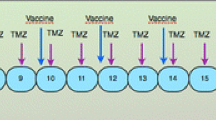

Treatment schedule: fully integrated radio–chemo–immunotherapy

Patients underwent maximum safe surgical resection of the tumor. Peri-operative corticosteroids were withdrawn within one week after resection. Leukapheresis was performed after histological diagnosis was obtained and inclusion criteria were met (Fig. 1). After leukapheresis, patients were treated with limited field external beam radiotherapy (30 × 2 Gy) and concomitant chemotherapy with TMZ (75 mg/m2) during six weeks as outlined by Stupp et al. [1]. After radiochemotherapy, tumor lysate-loaded DC were injected weekly for four weeks. Following these four weeks, TMZm chemotherapy was started. The maintenance 28-day cycles consisted of five days oral intake of TMZ (150 mg/m2 for the first and 200 mg/m2 for the following cycles). During the first, second, third, and sixth cycles, further boost vaccinations with tumor lysate (without DC) were administered at day 8 of the cycle. At the time of progression possible rescue therapy was at the physician’s discretion.

Treatment schedule. DC-based immunotherapy was integrated in the state-of-the art postoperative radiochemotherapy. Leukapheresis to harvest autologous monocytes is performed once, at least seven days after weaning off steroids and immediately before the start of the concomitant radiochemotherapy. After the radiochemotherapy, but before the maintenance chemotherapy with TMZ, four weekly induction vaccines are administered intradermally to the patient. Afterwards, maintenance chemotherapy (5/28 days) is started and one week after the start of the 1st, 2nd, 3rd, and 6th cycles of TMZ, a boost vaccine is administered